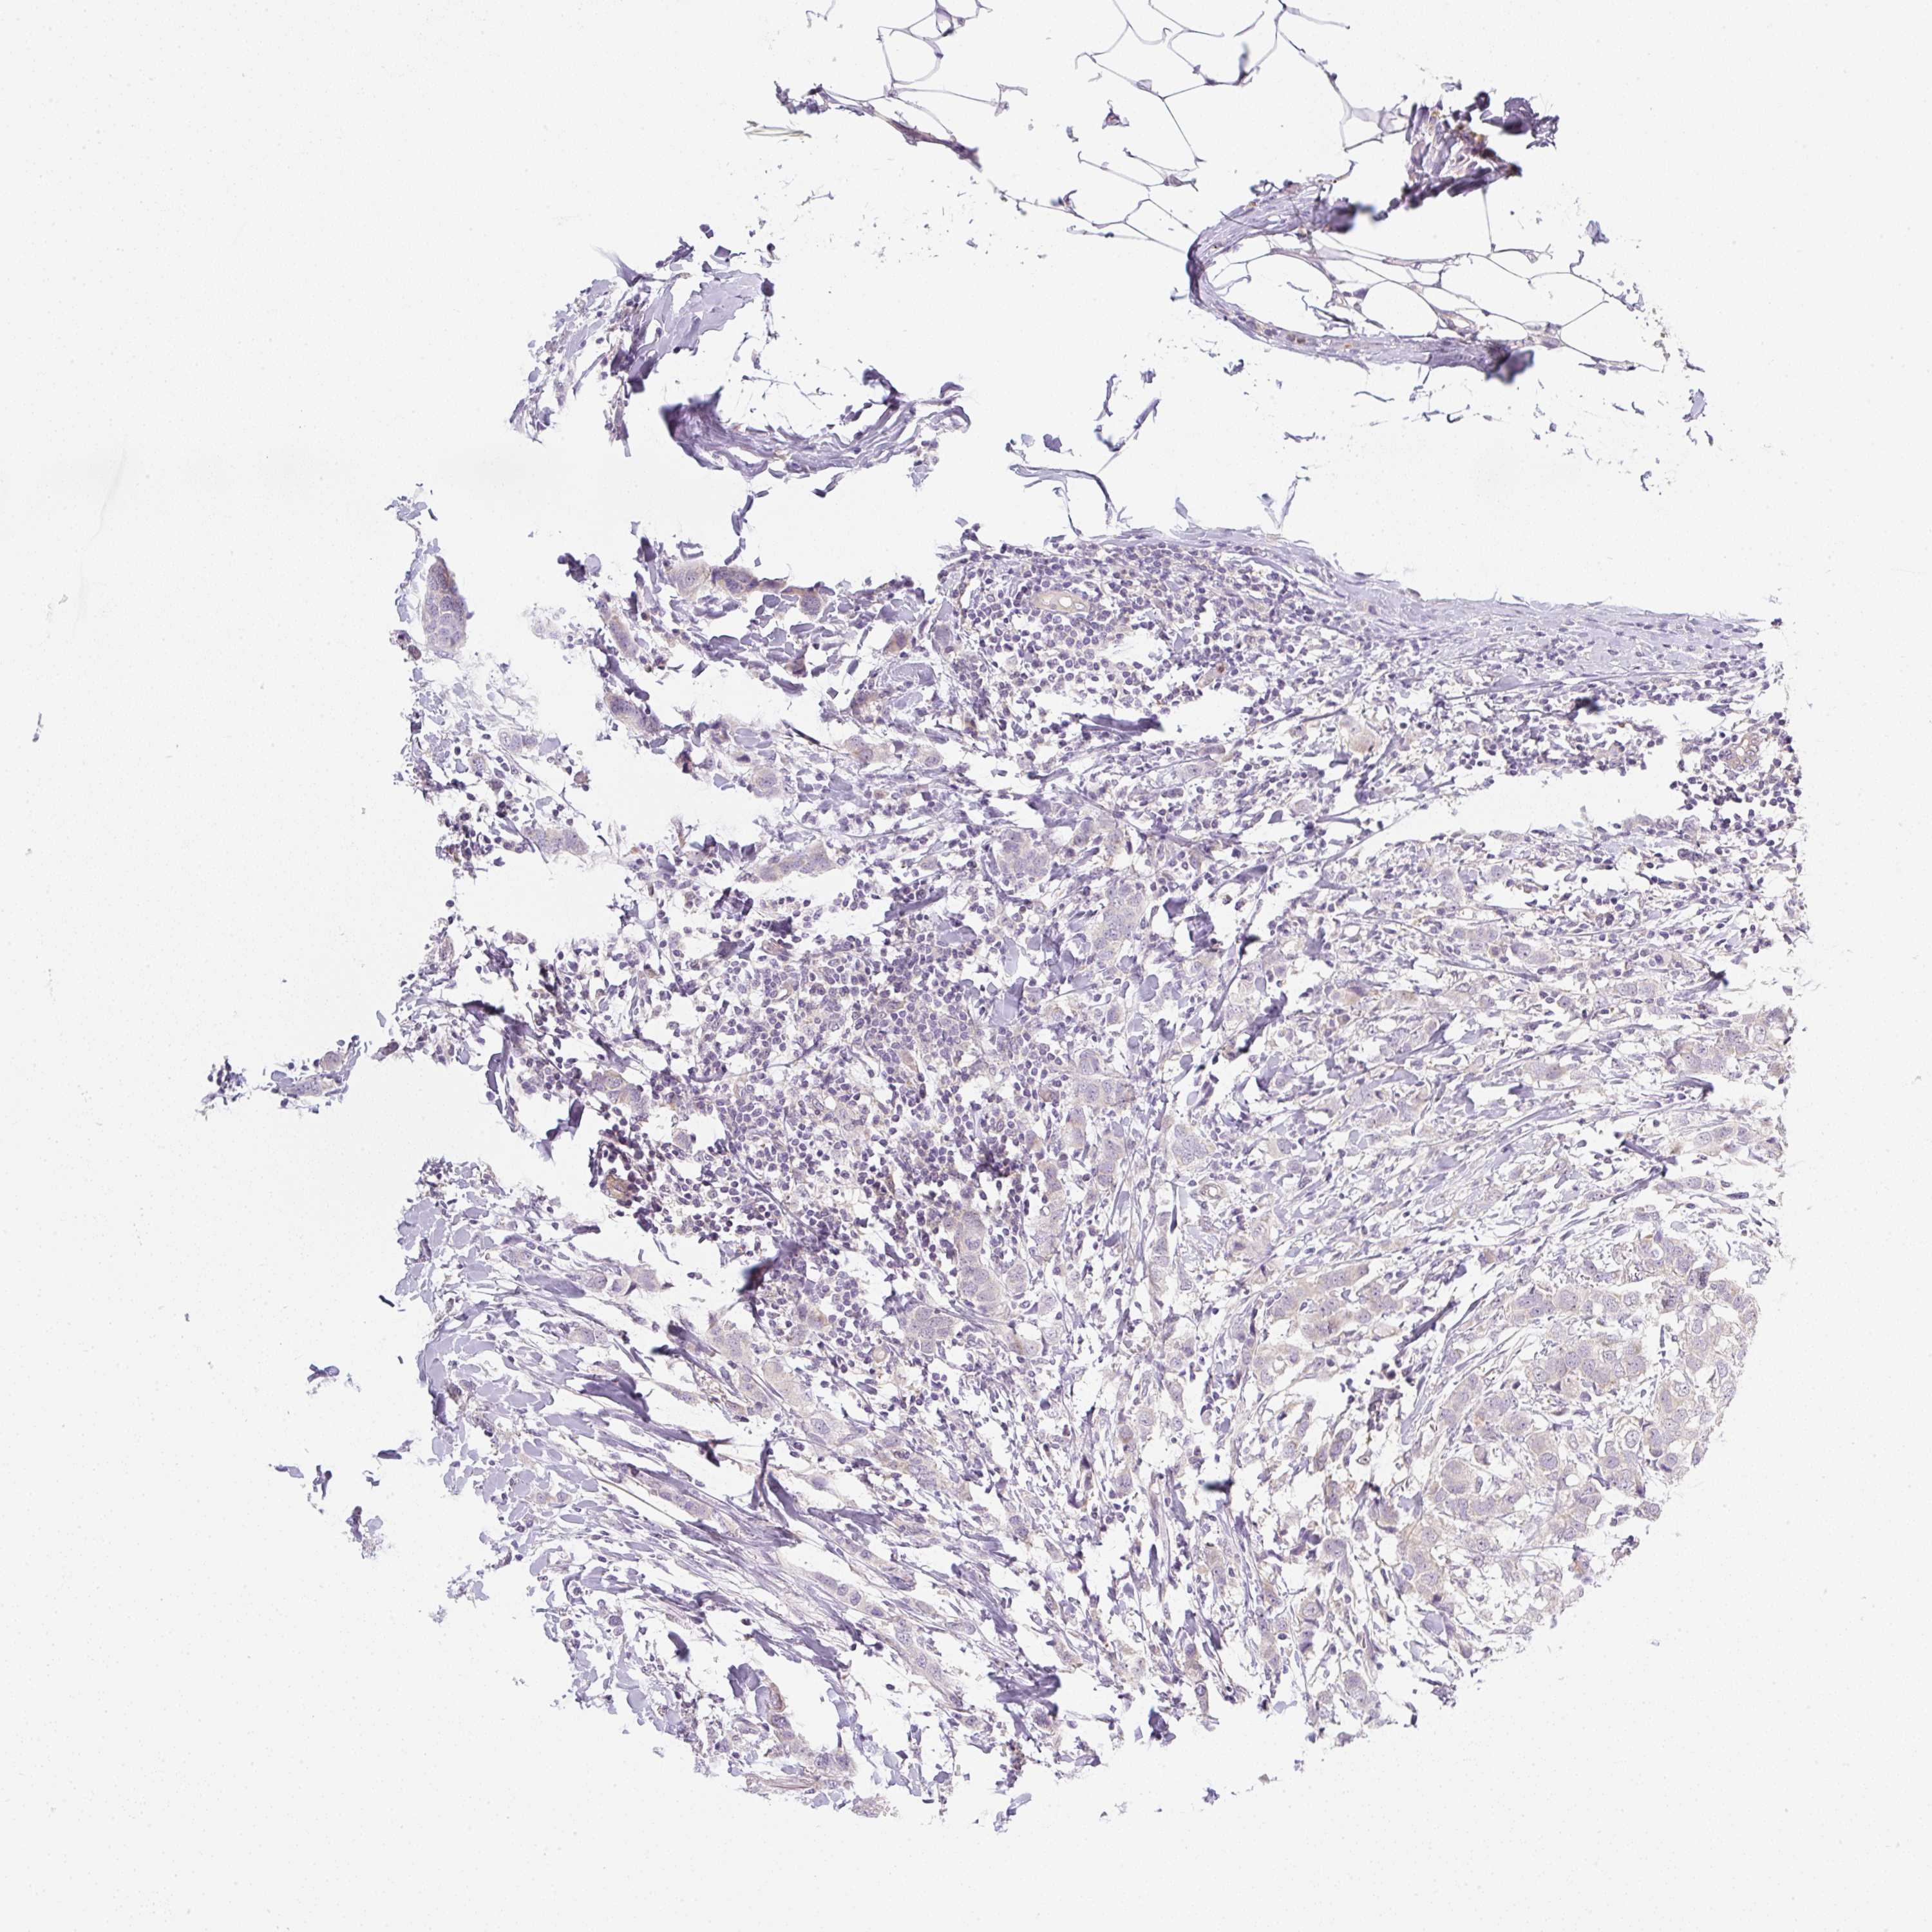

CANCER BREAST CANCER Show tissue menu

BRCA TCGA BRCA VALIDATION PROTEIN EXPRESSION

Breast cancer

Human cancer